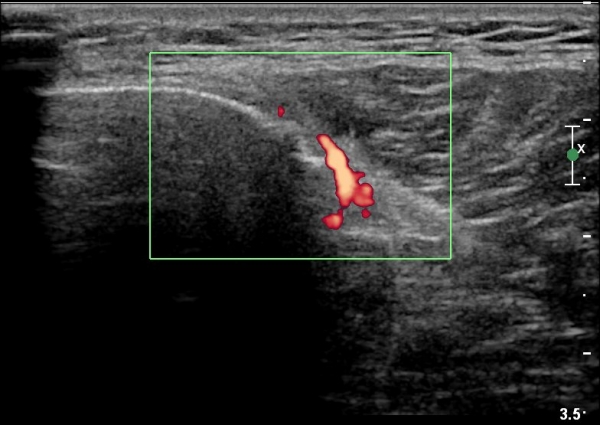

[¹«¸­] °æ°ñ ÇǷΰñÀý ÃÊÀ½ÆÄ¼Ò°ß(sonographic findings of stress fracture of tibia)

ÃÊÀ½ÆÄ °Ë»ç

¹Ì¼¼ÇÏ°Ô ¿¬ºÎÁ¶Á÷ ºÎÁ¾°ú °¡°ñ Çü¼ºÀÌ °üÂûµÊ.

Bilateral stress fracture of the tibia diagnosed by ultrasound. A case report